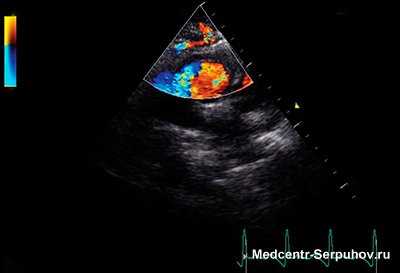

Выявить шум в сердце можно с помощью аускультации (прослушивания) сердечных тонов с помощью фонендоскопа. После этого педиатр рекомендует консультацию детского кардиолога, который проведет осмотр и направит на электрокардиографию (ЭКГ), чтобы выявить нагрузки на отделы сердца, а также эхокардиографию (ЭХО-КГ или УЗИ сердца), которая позволит точно выявить анатомическую причину шума. Затем детский кардиолог интерпретирует полученные данные. Для уточнения диагноза пациент может быть направлен на компьютерную томографию или магнитно-резонансную томографию, а если потребуется - и на ангиографию сердца.

*Основной метод диагностики причины шума в сердце - эхокардиография или УЗИ сердца. Желательно провести исследование в родильном доме, в 1 месяц, далее по показаниям: перед началом посещения детского сада, школы и спортивной секции.

Эхокардиография (ЭхоКГ) - это простое ультразвуковое исследование, только точкой приложения в нем является сердце. С помощью данного метода можно с высокой точностью определить источник шума или исключить порок сердца.